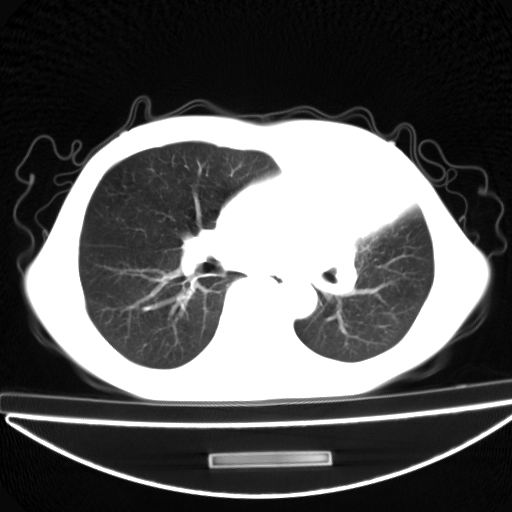

以下是引用杀毒软件在2009-4-28 17:58:00的发言:[br]考虑----左肺慢性肺脓肿形成继发上叶含气不良---抗炎后复查---待排肿瘤所致[br][br][本贴已被 杀毒软件 于 2009-4-28 18:01:26 修改过]